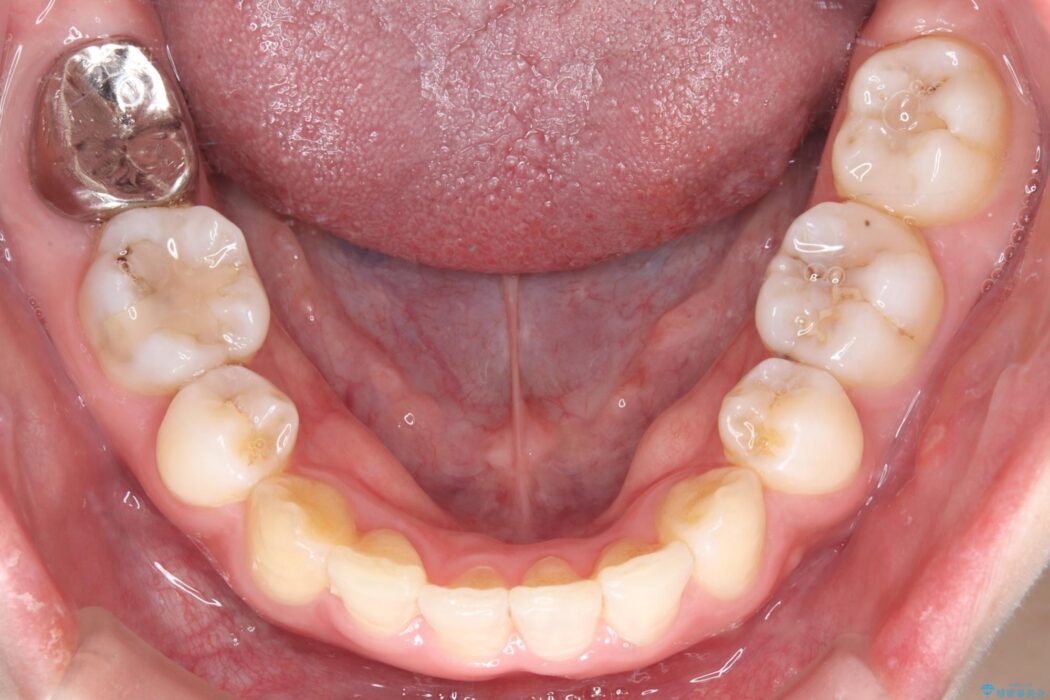

前歯から奥歯にかけて重度のがたつきを主訴にご来院された患者様です。

スペースが大きく不足し、口元を引っ込める必要があったため、上下左右4本抜歯による矯正治療を計画。目立たないインビザライン装置で、審美的なゴールを目指します。